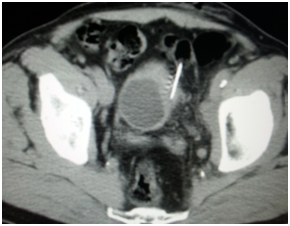

Endoscopy is the second diagnostic tool for this disease and during this procedure usually biopsies are taken -I did once percutaneous CT guided bladder biopsy (Figure 7) to assess the depth of tumor invasion of the bladder layers after insistence of the treating physician even though I think it's not necessary and cost ineffective.

Figure 7 Percutaneous CT guided bladder biopsy.